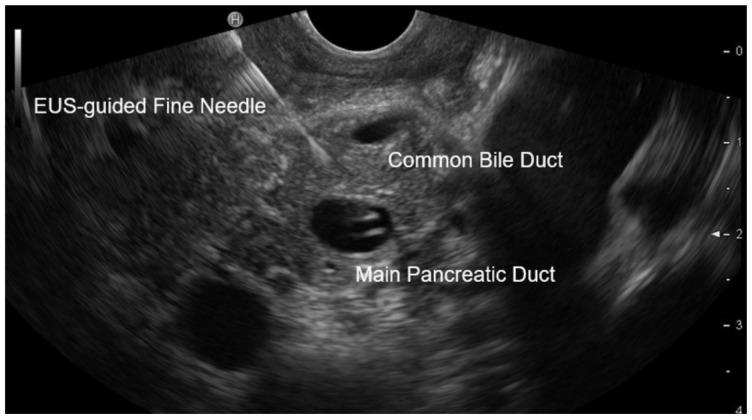

: A dilated main pancreatic duct (MPD) ≥ 5 mm can be observed in main-duct IPMNs (MD-IPMN) and chronic pancreatitis (CP); however, distinguishing between the two differently treated diseases can be difficult. Cell-free (cf) DNA in MPD fluid obtained by EUS-guided FNA might help to distinguish MD-IPMN from CP. : All patients with a dilated MPD ≥ 5 mm on EUS during the period of 1 June 2017 to 30 April 2024 were prospectively analysed in this single-centre study, with EUS-guided MPD fluid aspiration performed for suspected MD-IPMN or CP in patients who were suitable for surgery. Twenty-two known gastrointestinal cancer genes, including GNAS and KRAS, were analysed by deep targeted (dt) NGS. The results were correlated with resected tissue, biopsy, and long-term follow-up. : A total of 164 patients with a dilated MPD were identified, of which 30 (18.3%) underwent EUS-guided FNA, with 1 patient having a minor complication (3.3%). Twenty-two patients (mean MPD diameter of 12.4 (7-31) mm) with a definitive, mostly surgically confirmed diagnosis were included in the analysis. Only a fish-mouth papilla, which was present in 3 of 12 (25%) MD-IPMNs, could reliably differentiate between the two diseases, with history, symptoms, diffuse or segmental MPD dilation, presence of calcifications on imaging, cytology, and CEA in the ductal fluid failing to achieve differentiation. However, GNAS mutations were found exclusively in 11 of the 12 (91.6%) patients with MD-IPMN ( < 0.01), whereas KRAS mutations were identified in both diseases. : GNAS testing by dtNGS in aspirated fluid from dilated MPD obtained by EUS-guided FNA may help differentiate MD-IPMN from CP for surgical resection.

在主胰管内乳头状黏液性肿瘤(MD-IPMN)和慢性胰腺炎(CP)中均可观察到主胰管(MPD)扩张≥5mm;然而,区分这两种治疗方式不同的疾病可能具有挑战性。通过超声内镜引导下细针穿刺(EUS-guided FNA)获取的MPD液中的游离(cf)DNA可能有助于鉴别MD-IPMN和CP。:在这项单中心研究中,对2017年6月1日至2024年4月30日期间超声内镜检查发现MPD扩张≥5mm的所有患者进行了前瞻性分析,对适合手术的疑似MD-IPMN或CP患者进行了超声内镜引导下的MPD液抽吸。通过深度靶向(dt)二代测序(NGS)分析了包括GNAS和KRAS在内的22个已知胃肠道癌基因。结果与切除组织活检及长期随访结果相关。:共识别出164例MPD扩张患者,其中30例(18.3%)接受了超声内镜引导下细针穿刺,1例出现轻微并发症(3.3%)。分析纳入了22例确诊(大多经手术证实)的患者(MPD平均直径为12.4(7 - 31)mm)。仅12例MD-IPMN中的3例(25%)出现的鱼口样乳头可可靠地区分这两种疾病,病史、症状、MPD弥漫性或节段性扩张、影像学上钙化的存在、细胞学检查及导管液中癌胚抗原(CEA)均无法实现鉴别。然而,12例MD-IPMN患者中有11例(91.6%)仅发现GNAS突变(<0.01),而两种疾病中均发现了KRAS突变。:通过超声内镜引导下细针穿刺从扩张的MPD抽吸液中进行dtNGS检测GNAS可能有助于鉴别MD-IPMN和CP以指导手术切除。